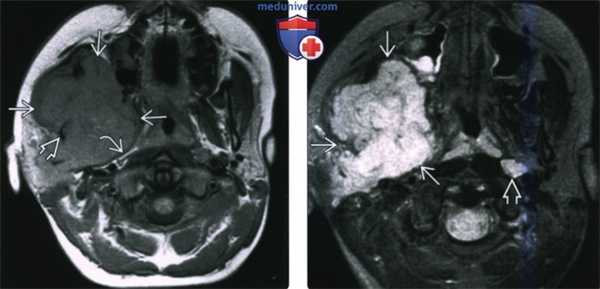

(Слева) На аксиальной КТ в костном окне визуализируется типичная хондросаркома ВНЧС с множественными кальцинатами. Мыщелок нижней челюсти слева неравномерно склерозирован, в ВНЧС и вокруг него визуализируются множественные мелкие очаговые кальцинаты.

(Справа) На сагиттальной реформатированной КТ у этого же пациента определяется деформация мыщелка. Некоторые кальцинаты, вероятно, находятся в мягкотканном компоненте за пределами сустава.

(Слева) КТ в костном окне, аксиальная проекция. Типичная хондросаркома левого височно-нижнечелюстного суаава. Мыщелок нижней челюсти склерозирован и имеет неправильную форму, внутри и вокруг сустава рассеянны множественные кальцификаты. И хотя в данном случае достаточно сложно дифференцировать заболевание от синовиального хондроматоза, в обоих случаях лечение должно быть хирургическим, а точный диагноз будет установлен после гистологического исследования.

(Справа) Реконструкция в сагиттальной плоскости, этот же пациент. Мыщелок деформирован, а часть кальцификатов находится в мягких тканях вне сустава.

(Слева) КТ в костном окне, аксиальная проекция. Типичная хондросаркома височно-нижнечелюстного сустава низкой степени злокачественности. Определяются небольшие кальцификаты дистрофической природы (либо кальцифицированный матрикс самого образования) и обширная деарукция/ремоделирова -ние суставной ямки.

(Справа) MPT Т2ВИ в аксиальной проекции, тот же пациент. Определяется дольчатое гиперинтенсивное образование с четкими контурами, которое окружает мыщелок нижней челюсти.